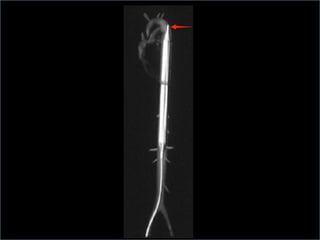

 Balloon should be positioned so that the tip is

about 1-2 cm distal to the origin of the left

Confirmation of position

 arterial balloon waveform and pressures shown

 Chest x-ray or fluoroscopy

radiopaque tip lies in the 2nd intercostal spaces

just above the left main bronchus; lower end of

balloon should lie cephalad to the renal arteries